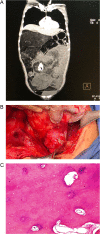

Liposarcomas are rare malignant tumors that mostly develop in the retroperitoneum. They have a broad behavioral spectrum, from small masses of tissue to highly aggressive tumors. The dedifferentiation process occurs in up to 10% and it's most likely to occur in the retroperitoneum, a process that not only changes its components but also its prognosis. These tumors can grow to a massive size since most of them do not give any symptoms until they invade the adjacent structures. Timely detection and surgery could avoid all these potentially lethal scenarios. We present a case of a 34-year-old patient, who reported a growing mass in her abdomen that reached massive proportions but remained untreated due to lack of sufficient access to healthcare facilities in her geographic location. After complete removal of the mass the patient underwent complete recovery, dedifferentiated liposarcoma was the final diagnosis.